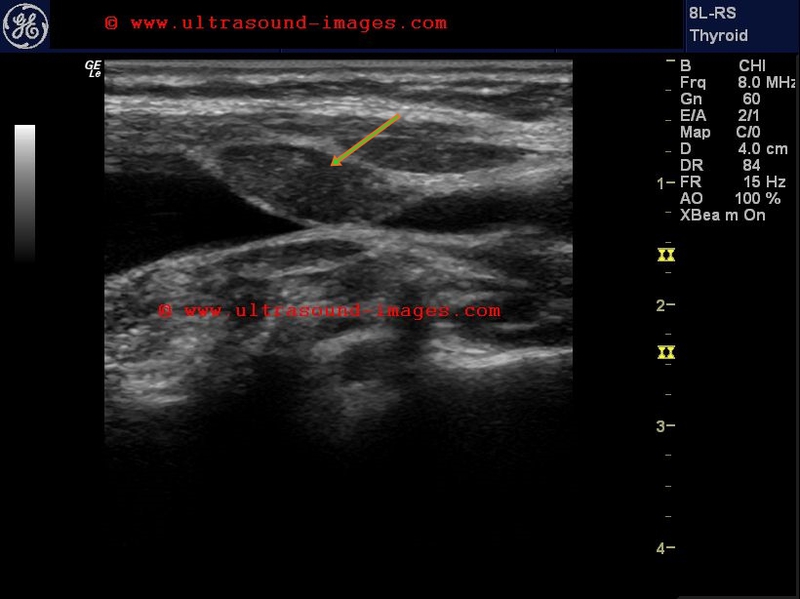

De-Quervains-thyroiditis-or-subacute-thyroiditis

This elderly female patient presented with pain in the neck and intermittent fever. Ultrasound imaging of the thyroid gland shows markedly hypoechoic lesions in the right lobe. Color and Power Doppler ultrasound failed to show significant vascularity within the affected area (lesion) in the right lobe. The hypoechoic thyroid lesion shows irregular borders and is seen to infiltrate along the long axis of the affected lobe. Follow up ultrasound images show that the lesion has increased in size and also shows patchy involvement of the left lobe also. Again there is no vascularity in the affected hypoechoic lesions and marked tenderness is presented in these lesions on probe pressure. These sonographic findings are suggestive of De Quervain's thyroiditis, also known as subacute thyroiditis.